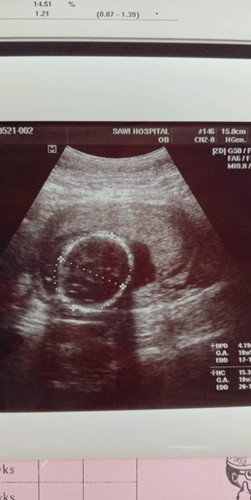

อัลตราซาวนด์

บ้านนี้ฝากคลินิก หมอจะบอกตลอด ตรงนี้หัวนะแม่ ตรงนี้มือ มือซ้ายอยู่ตรงนี้นะ มือขวาน้องนอนทับอยู่นะ มีกระเพาะอาหาร มีเส้นเลือด ขาน้องรอบนี้นอนชี้ฟ้าเลยแม่ หมออธิบายละเอียดมากค่ะ เราแทบไม่ต้องถามเพิ่มเลย แต่ถ้าอันไหนที่มองไม่เห็นหมอก็จะแจ้ง อย่างล่าสุดน้องนอนทับมือตัวเอง หมอก็บอกรอบหน้าหมอจะดูตรงนี้ให้นะแม่ที่ยังมองไม่เห็น

อ่านเพิ่มเติมนี่หัวน้องค่ะ ต้องดูตอนหมอซาวค่ะจะไล่ไปทีละส่วนให้ดู หัว สมอง แขนซ ข มือซ ข ขาซ. ข. เท้าซ. ข. ปากแหว่งไหม พุง หมอบอกละเอียดยิบเลยค่ะบ้านนี้

อันนี้เป็นส่วนหัวกับตัวของน้องคะ